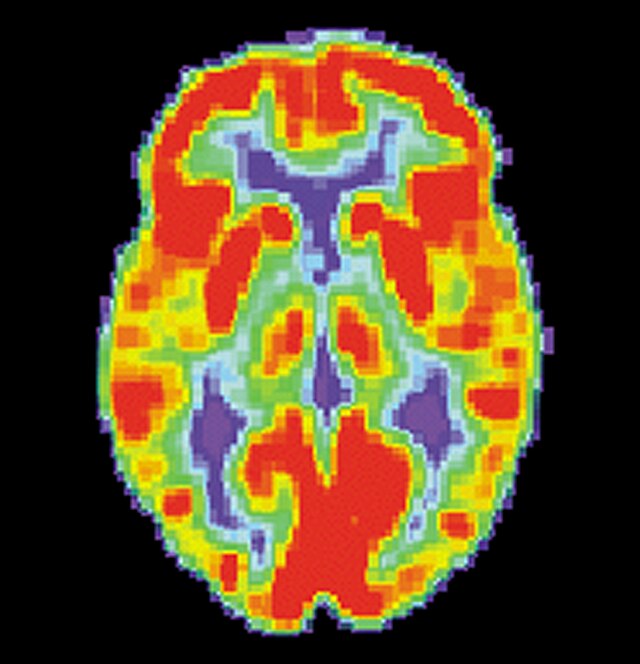

- 1.2 Examples of homogeneity in medical imaging modalities illustrating the similarity of the underlying subject (PET, CT, and MRI).

- (a) PET scan of the brain77footnotemark: 7

Thirdly, while seeming counter to the second point, while in a broad sense medical images are heterogeneous due to the very different imaging techniques and separation based on medical specializations (head scans vs foot scans), within a given data type, there is very high visual similarity. For example, all chest X-rays will look very similar due to standardized acquisition methods and tools, but also in large part, due to the high homogeneity of the human biology, see figure 1.2. For the chest scan example, most human bones and organs will have almost identical structures, similar sizes, and composition. Furthermore, the way these scans are collected is standardized, so the patients will all be positioned at the same angle and distance from the imaging machines. This is true even for data samples that have completely different labels, as the characteristics that indicate one diagnosis or another are often identified by very small, granular differences, which are visually very small in absolute terms. This poses a challenge to researchers in the sense that they can’t directly adapt many of the more recent and best-performing classes of Self-Supervised methods, such as contrastive learning. This has allowed us to develop methods that are tailored specifically for medical images.